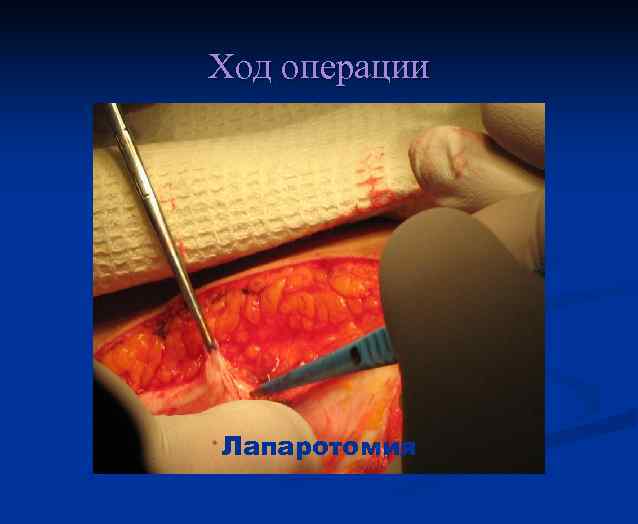

Ход операции Лапаротомия